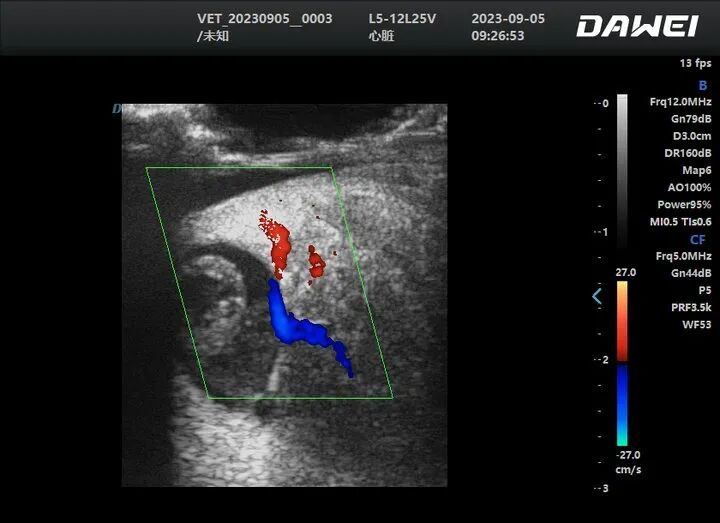

5. Shellfish ultrasound / bivalve ultrasound Case

Objective

- Measure heart rate changes in oysters and scallops under different water temperature conditions, to support aquaculture research and provide practical guidance for farmers.

System

- Dawei L5-VET Laptop Veterinary Color Doppler Ultrasound

- Probe: High-frequency linear transducer (for better superficial-detail imaging)

How it’s used

- Researchers perform ultrasound scanning and record heart rate signals at different temperature settings, then compare trends across groups.